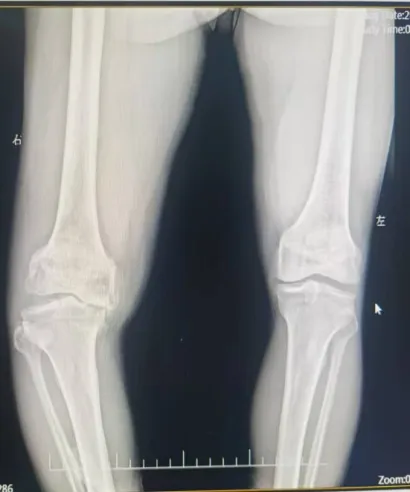

今年68岁的何爷爷是一位典型的右膝重度骨关节病患者。他右膝内翻畸形严重,行走时存在明显的跛行现象及O型腿,膝关节屈伸角度受限,下蹲困难,内侧胫骨平台缺损多,下肢力线极差,手术难度极大。多年来他饱受右膝疼痛的折磨,尤其在上下楼梯或长时间站立时,疼痛感更是明显加剧。